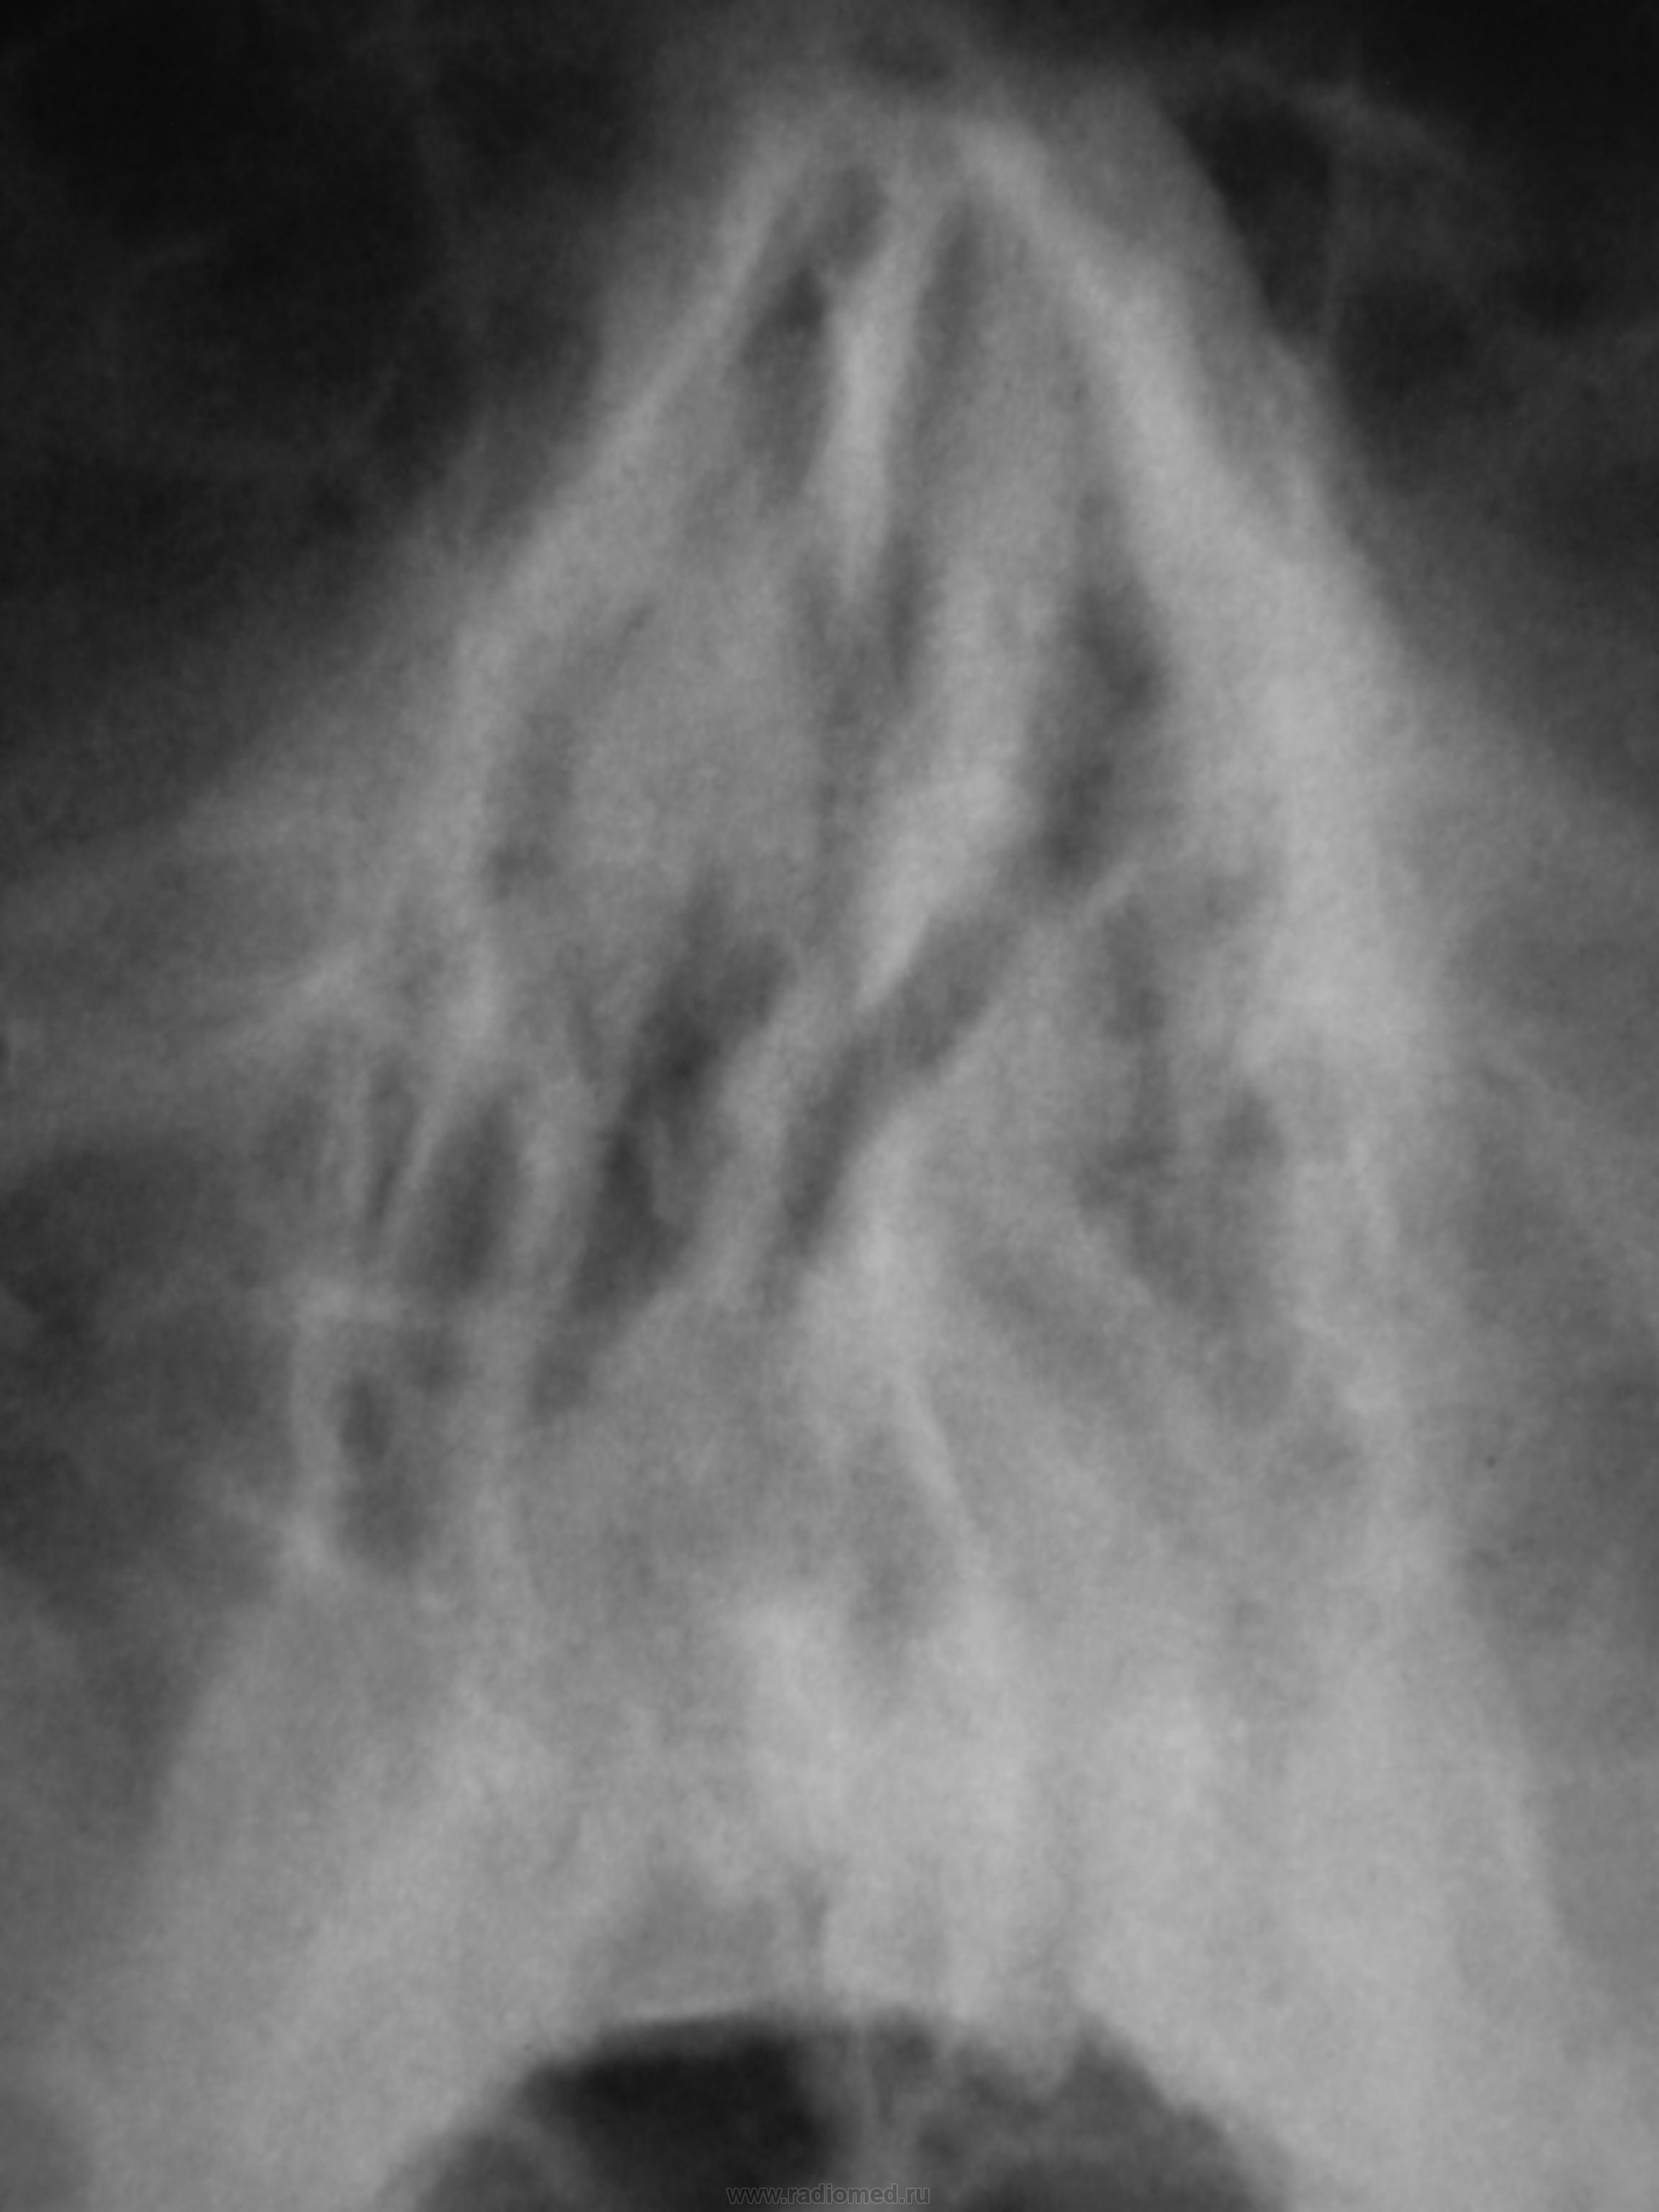

Пациент направлен для рентгенографии ППН, готовится к операции «на глазах».

гиперпластический гайморит.

Двусторонний гайморит и искривление носовой перегородки.

Довольно "хитрое" искривление...

Буквой "зю")))

Простите пожалуйста, дорогие коллеги, что снова как на танке врываюсь) Очень интересные ППН, во всяком случае ранее не видел. Парень 19 л. с правосторонней  "шиповидной" деформацией н/3 носовой перегородки и ... Как изменения правой гайморовой пазухи интерпритировать? Я так и заключил, изменения правой гайморовой необходимо дифференцировать между склерозом (хронич.гайморит) и гипоплазией. Подскажите мне зелёному пожалуйста, у кого опыта больше, что тут вероятнее всего?